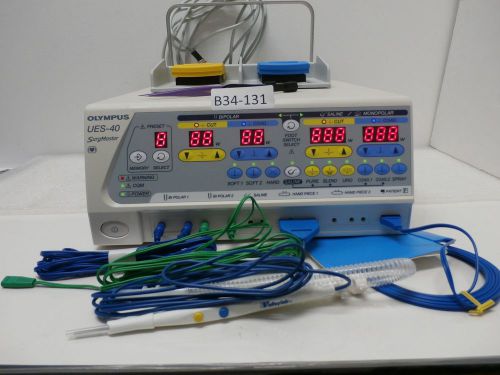

Olympus UES-40 SurgMaster ESU Processor W-Foot Switch & Bipolar forceps & Cable